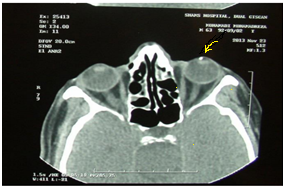

In addition, dilated fundus examination of the left eye did not reveal any pathologic abnormalities in the anterior vitreous. The disk and macula were intact in the left eye. The axial and coronal orbit CT scan results reported a metallic foreign body near by the anterior surface of left lens (Figure 3). Scotopic ERG determined a wave amplitude 30 dB and b wave 78 dB, that indicative for mild decrease in both amplitude waves. Photopic ERG did not show any changes in amplitude waves. Decrease of visual acuity is justifiable with nuclear cataract sclerosis and mild uveitis. The patient treated with topical anti-inflammatory (eye drop betamethasone) and mydriatic/cycloplegic (eye drop homatropine) and followed up for response to our medication.

Figure 3 Intraocular foreign body in axial view of orbital CT.